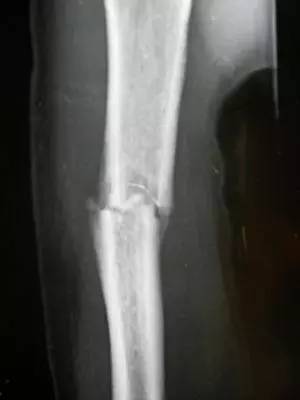

男42岁,跟骨骨折

伤筋动骨一百天的思考

跟骨骨折87天了专家们给看看!